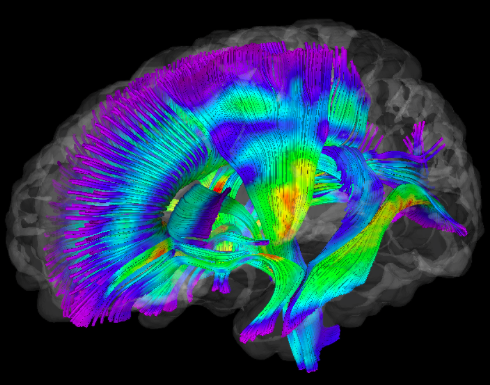

Imaging Data

2. Visualisation:

- Visualization - 3D and 4D

BrainBrowser

..a set of web-based 3D visualization tools primarily used for viewing neurological data i.e. MRI scans.

It allows for real-time manipulation and analysis of 3D neuroimaging data through any modern web browser. TRY ME!

BrainBrowser - 3D Surface Viewer